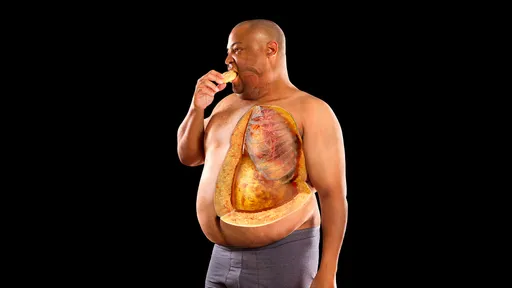

Obesity